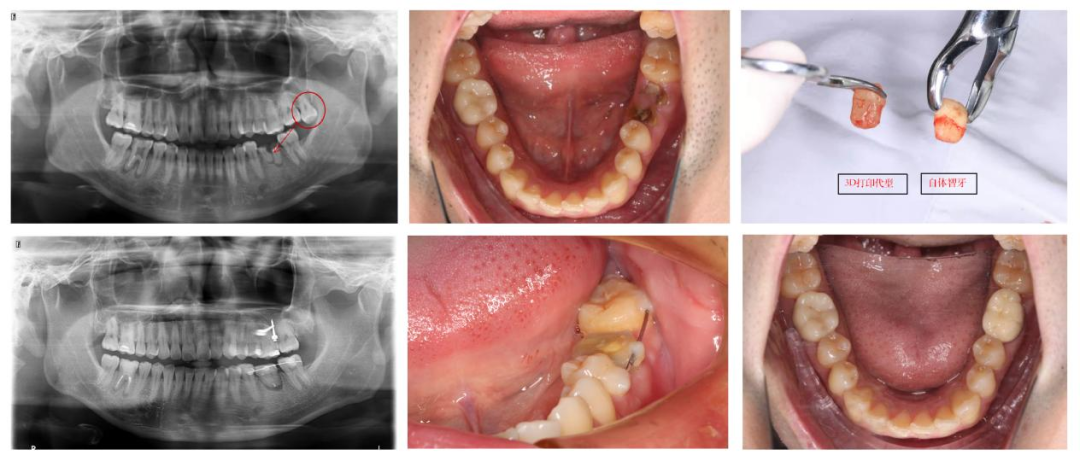

然而,随着计算机技术的高速发展,自体牙移植技术聚集了目前大部分口腔先进治疗技术,如微创拔牙术、牙槽骨及牙周组织再生技术、数字化导板技术和种植技术等等,目前成功率可以达到86.67%,存留率达96.67%。有学者进行15年随访,成功率可以达到81%,存留率达88.37%。本科室组织口腔各科室专科专家进行术前讨论,已通过计算机数字化辅助技术,利用3D打印技术制作智齿模型,在数字化导板引导下精准备洞,调整空缺位置,给智齿建成一个合适的“新家”,给它一次做有用牙齿的机会。本科室对自体牙移植具有丰富的经验,预后较好,获得了患者的认可和好评。